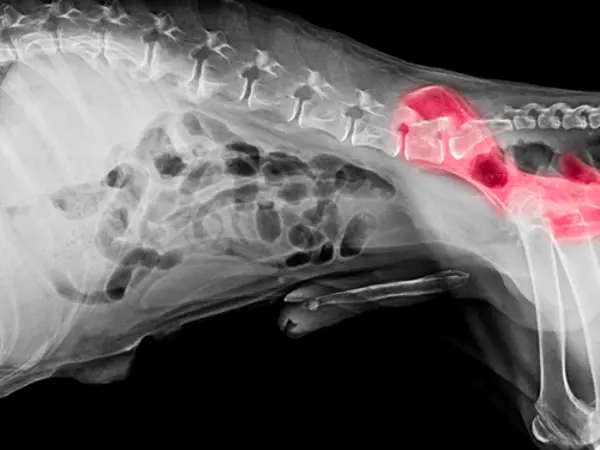

Ortopædi

Skovshoved dyreklinik har special kompetence indenfor ortopædi og fungerer som henvisningsklinik for patienter med ortopædiske lidelser.